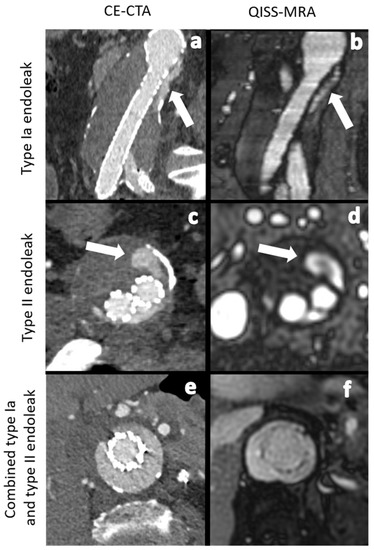

| Type Ia | 1 (6.2%) | 1 (8.3%) | 1 | Type Ia | 1 (7.1%) | 1 (9.0%) | 1 | ||

| Type Ib | 3 (18.7%) | 3 (25.0%) | 1 | Type Ib | 3 (21.4%) | 3 (27.0%) | 1 | ||

| Type II | 11 (68.7%) | 8 (66.7%) | 0.71 | <0.01 | Type II | 9 (64.2%) | 7 (63.6%) | 0.79 | <0.01 |

| Type III | 0 (0%) | 0 (0%) | Type III | 0 (0%) | 0 (0%) | 1 | |||

| Type V | 1 (6.2%) | 0 (0%) | Type V | 1 (7.1%) | 0 (0%) | ||||

| Total number | 16 | 12 | Total number | 14 | 11 | ||||

| Type Ia | 1 (6.2%) | 1 (7.1%) | 1 | Type Ia | 1 (8.3%) | 1 (9.0%) | 1 | ||

| Type Ib | 3 (18.7%) | 3 (21.4%) | 1 | Type Ib | 3 (25.0%) | 3 (27.2%) | 1 | ||

| Type II | 11 (68.7%) | 9 (64.2%) | 0.80 | <0.01 | Type II | 8 (66.7%) | 7 (63.6%) | 0.89 | <0.01 |

| Type III | 0 (0%) | 0 (0%) | 1 | Type III | 0 (0%) | 0 (0%) | 1 | ||

| Type V | 1 (6.2%) | 1 (7.1%) | 1 | Type V | 0 (0%) | 0 (0%) | 1 | ||

| Total number | 16 | 14 | Total number | 12 | 11 | ||||